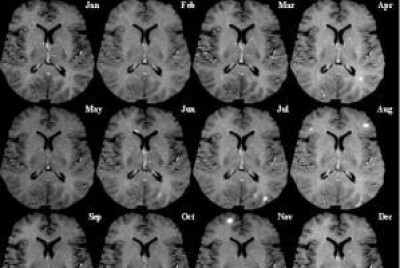

Padova, 6 mag. 2013 - A Padova città e provincia negli ultimi dieci anni sono raddoppiati i casi di sclerosi multipla e, secondo la squadra della Clinica Neurologia dell’ospedale di Sant’Antonio, i fattori ambientali, quindi l'esposizione ai contaminanti presenti in aria, acqua, cibo e suolo sono fondamentali per lo sviluppo della patologia. Il Registro dei Tumori del Veneto in una recente indagine ha valutato l’esposizione ambientale a diossine prodotte da inceneritori in tre ULSS della provincia di Venezia, il risultato è che il rischio di linfomi non Hodgkin è quasi raddoppiato nelle donne veneziane che vivono in prossimità a questi impianti. I risultati dello studio sono in accordo con altre recenti evidenze di una relazione tra esposizione ambientale a diossine e insorgenza di neoplasie, in particolare sarcomi e linfomi non Hogkin. Chiediamo alle autorità sanitarie locali perché non è mai stata fatta una indagine epidemiologica sulla popolazione che risiede nell’area di ricaduta dei fumi dell’inceneritore di Padova. Da cinquant’anni anni la popolazione è sottoposta ad una forte pressione ambientale prodotta dall’impianto situato nel quartiere Forcellini, a cui si aggiunge l’attività quarantennale dell’acciaieria di Camin. La popolazione infantile dell’area vive in una zona a rischio cancro per bambini, così definita da una ricerca dell’istituto Mario Negri di Milano. Chiediamo al sindaco e alle autorità sanitarie come mai nessuna indagine è stata fatta e nessuna informazione adeguata è stata fornita alla popolazione. Padova è una città che respira aria malata, nel corso dell’anno i livelli sanitari di polveri sottili ed ozono sono superati uno giorno si ed uno no, il benzoapirene, cancerogeno certo, è sempre sopra limiti dal 1999. Chiediamo al sindaco e alle autorità sanitarie perché il registro dei tumori della Ulss 16 non è più attivo dal 1999? Chiediamo al sindaco e alle autorità sanitarie lo cali se la prevenzione sanitaria è stata sospesa.

Aumento sclerosi multipla a Padova